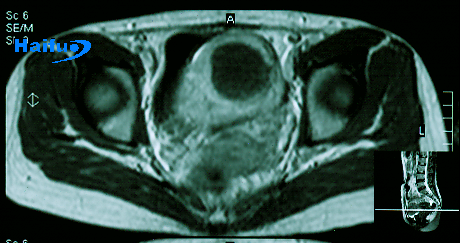

治疗后2周